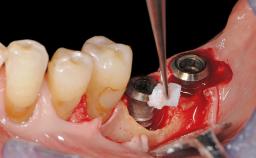

In this case, Myroslav Solonko, Ignacio Sanz Sánchez and Mariano Sanz present a treatment that aims to eliminate exposed implant threads by modifying the implant surface, converting a moderately-rough surface into a smooth surface.

A 63-year-old male patient was referred to the post-graduate periodontal clinic of the Complutense University of Madrid for the treatment of peri-implantitis. According to the patient’s record, all his maxillary teeth had been extracted ten years previously due to severe periodontitis, and a full-mouth implant-supported restoration on eight implants was placed. No supportive periodontal therapy was provided apart from occasional check-ups by the restorative dentist.